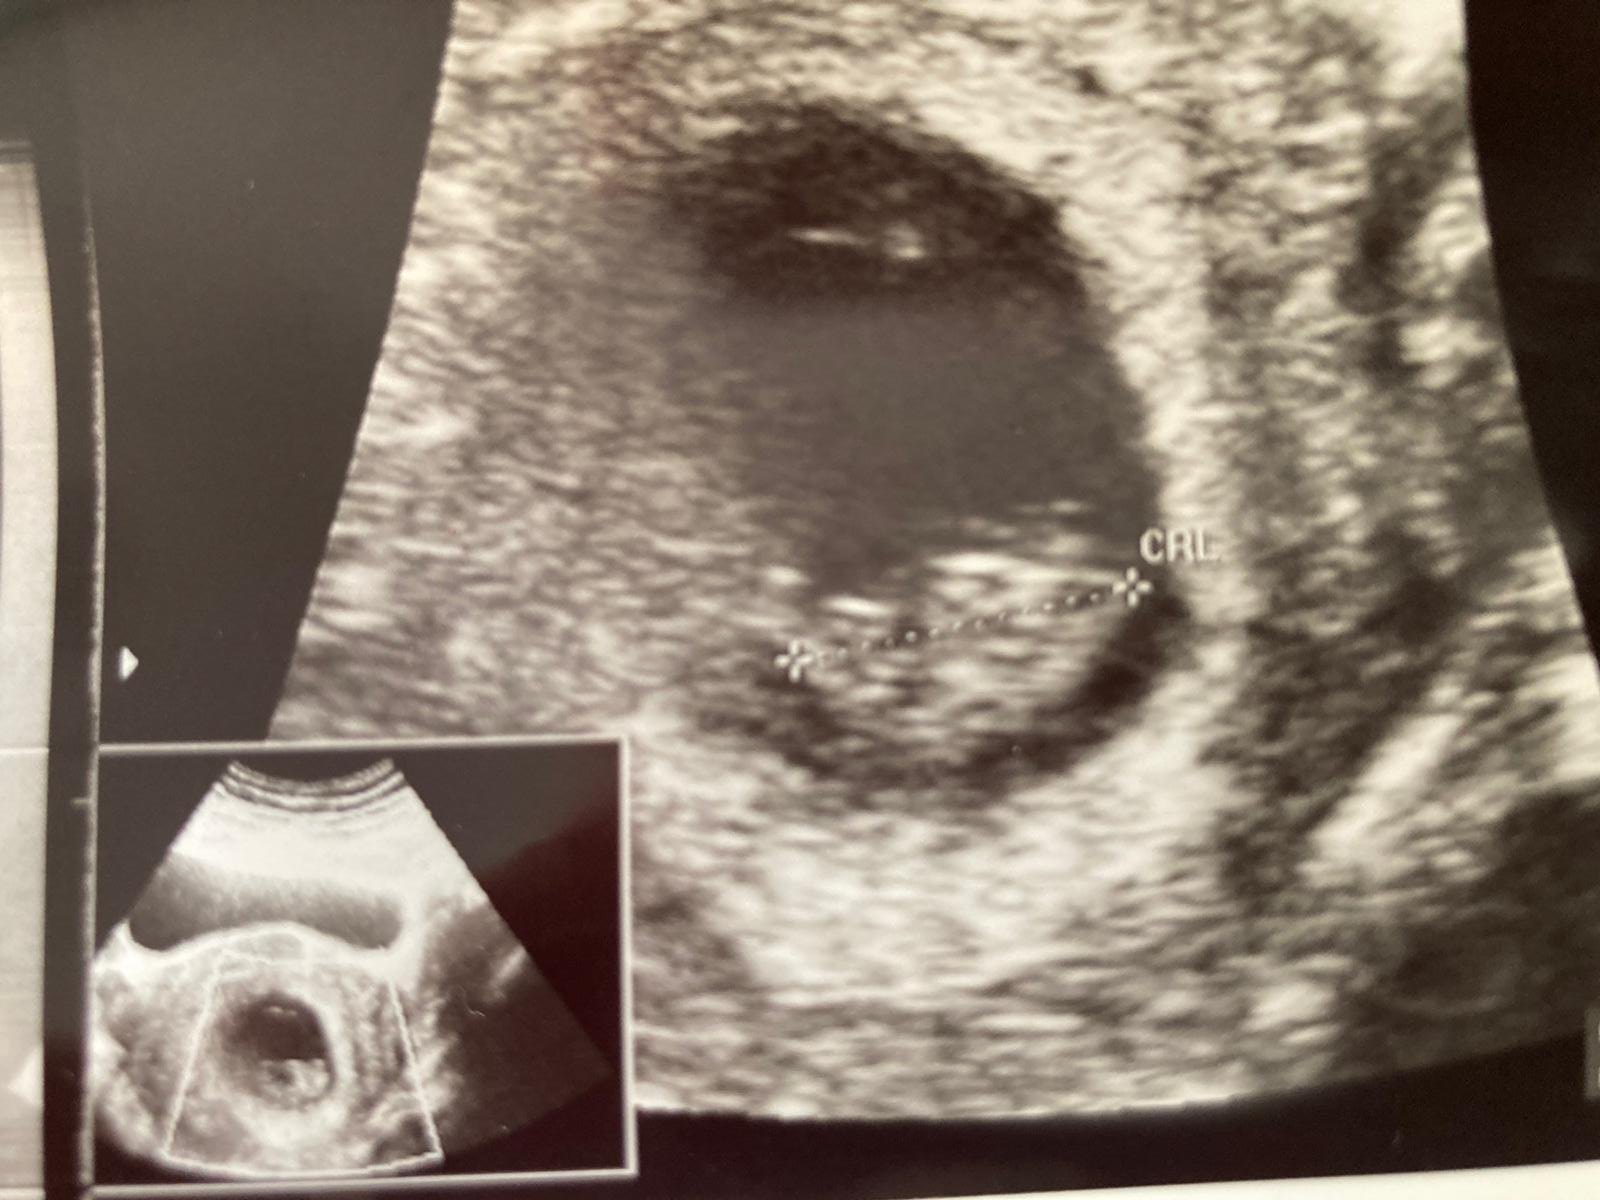

Selamlar hayırlısı hayatım senin bebişinin ramzi teorilik durumu yok. Aşağıda linkini veriyorum NUB TEORİSİNE GÖRE CİNSİYET tahmini yapıyorum. Başka resim var ise daha başka ekle hayatım ama eklediğin resme bakılır ise KIZ gibi görünüyor. Gaybı Allah bilir biz sadece gördüğümüzü söyleyebiliriz 🙂

Malesef hayatım resmin resmini çekerken net çekemiyorsun gen eyorum yapamıyorum gene kız gibi görünüyor diyebilirim nuba göre 🙂